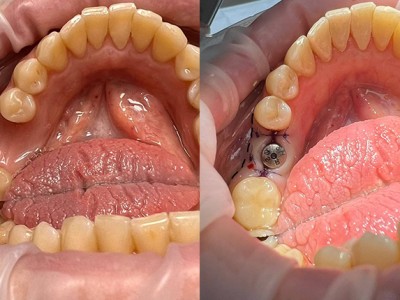

- Истории пациентов - Стоматология